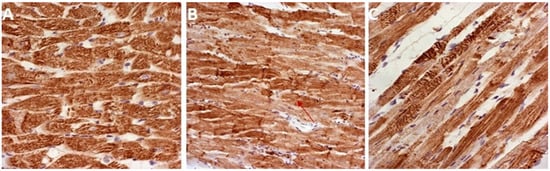

3.7. Histopathological Analysis

| Groups | Score |

|---|---|

| CTRL | 0.8 |

| DOX | 3.5 |

| DOX + GVE | 2.5 |